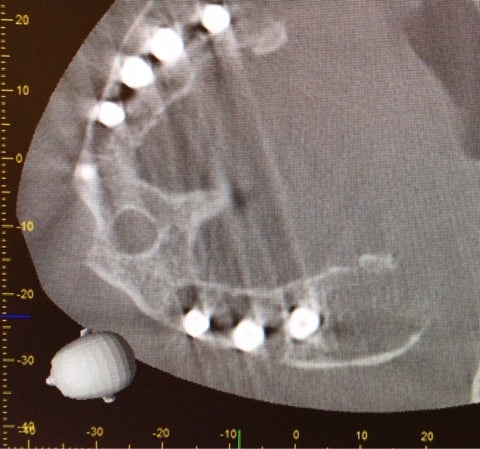

3次元的に精査する必要もある状態であったためCT撮影も行いました。

<CT画像>

▶︎CTからもインプラントを取り囲む顎骨の吸収が確認できました。